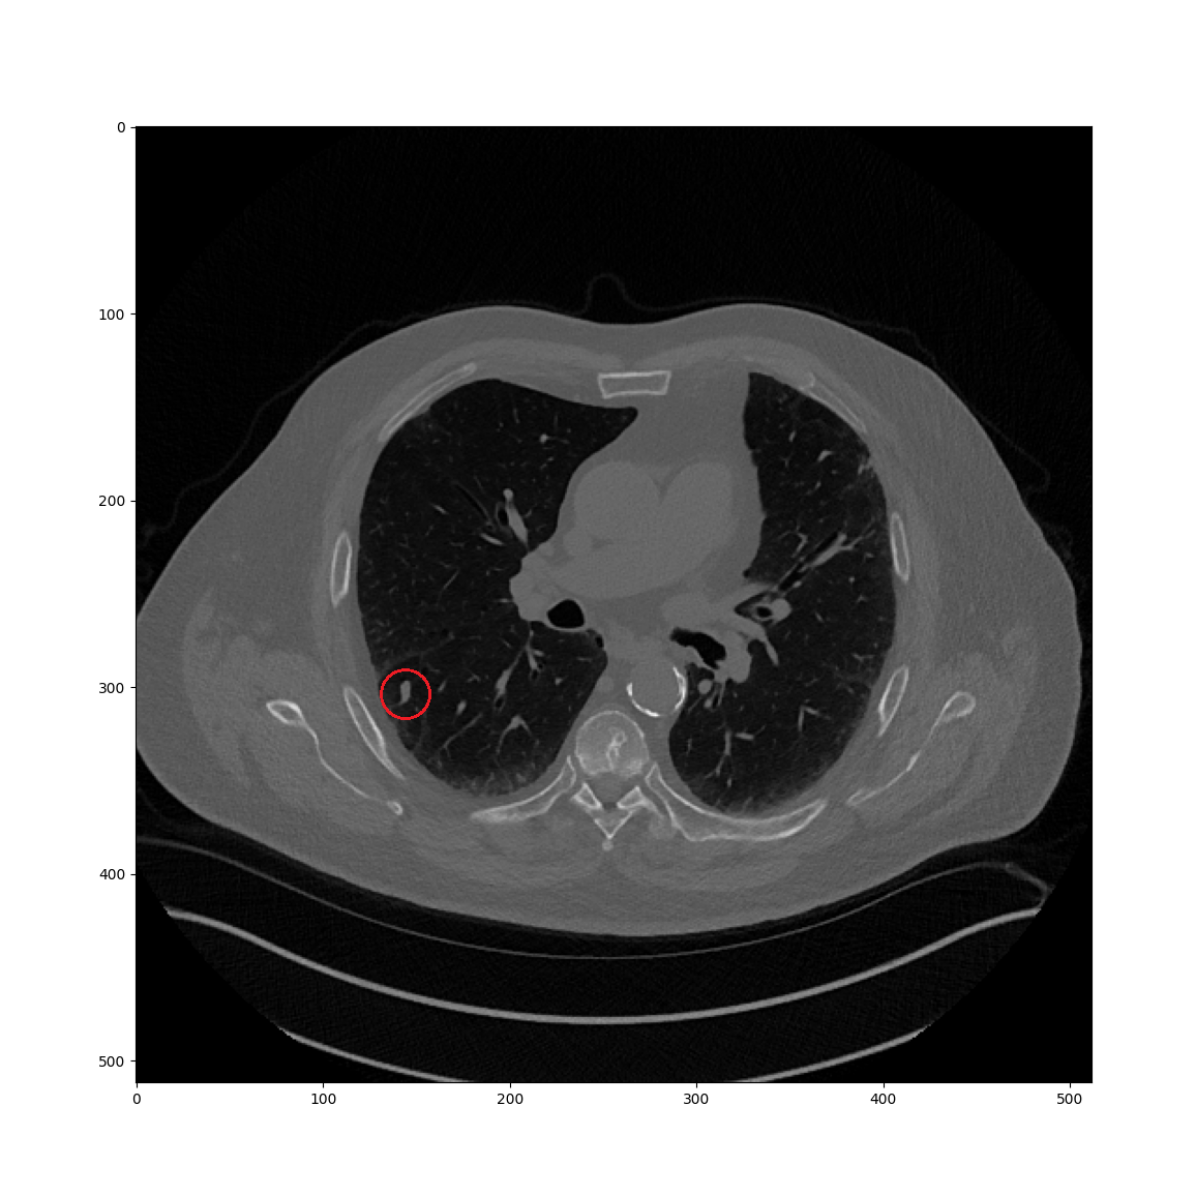

In Figure 2(a), there is a lung nodule at the point of interest of the current CT volume as an example of query point. The task is finding the corresponding location in the prior CT volume as shown in 2(b). In the first level, similarities are computed in every location of the 16mm grid which could be seen as a low-resolution heatmap as in 2(c). Then, until the fifth level, the maximum similarity location is used to continue the search in the next level while reducing the size of the search region. The resulting heatmap is given in Figure 2(d). The similarity in the finest level precisely describes the nodule location. There are two different characteristics as compared to the deep learning-based descriptor search approach [17]. First, the finest similarity is not computed on the whole image but on a specific location conditionally on the previous maximum. Thus, our algorithm is computationally faster, even on the CPU. Also, the descriptor is based on a predefined sampling model, which does not require optimization in training time or any additional computation for feature extraction in the runtime.